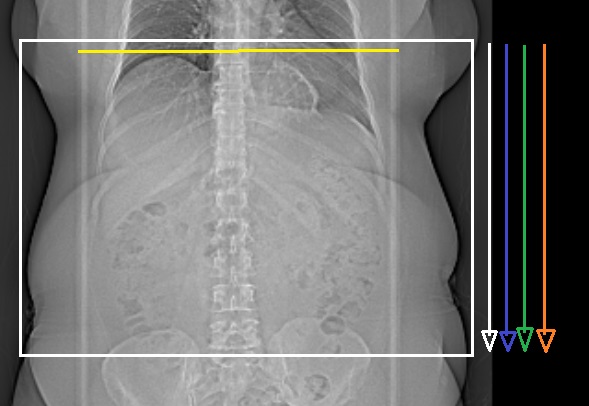

Övre buk före kontrast, i artärfas, porta/pancreasparenkym fas samt i portovenös fas